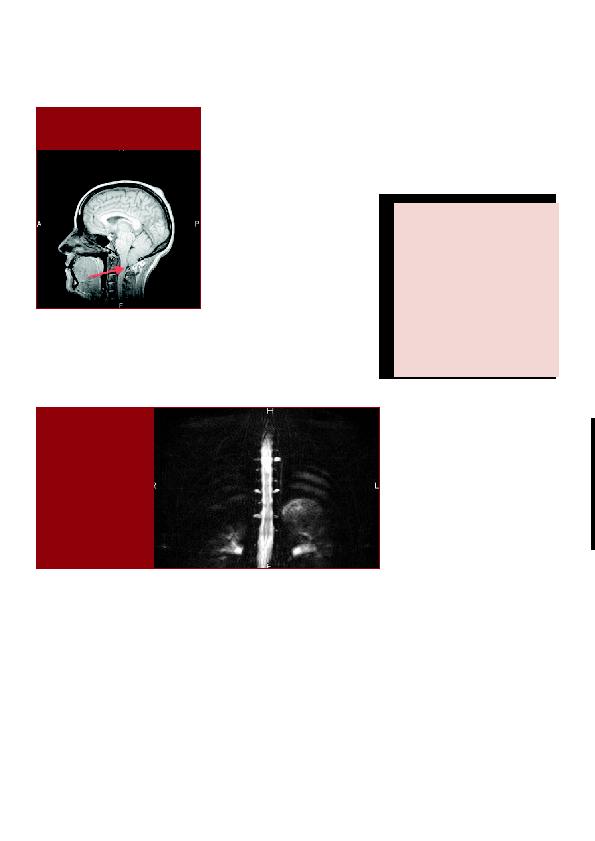

La RMN de l'encéphale de notre patiente

montre une descente des amygdales cé-

rébelleuses et de la partie inférieure du

vermis sous le niveau du trou occipital

avec descente également du tronc céré-

bral compatible également avec une hy-

potension intracrânienne.

Les séquences myélographiques (RMN)

de la totalité de la moelle épinière

mettent en évidence la présence des

multiples kystes radiculaires aux niveaux

dorsal et sacré. Nous postulons que

Figure 2: Séquence

myélographique de la

moelle épinière montrant

plusieurs kystes radiculaires

orsaux et lombaires.

Figure 1: Descente des amygdales

cérébelleuses et de la partie inférieure du

vermis sous le niveau du trou occipital.

plus de 1,5cm sous le niveau du trou

occipital (Figure 1).

L'IRM de la moelle épinière montre la

présence des multiples kystes radiculaires

aux niveaux dorsal et sacré sans brèche

durale mise en évidence (Figure 2).